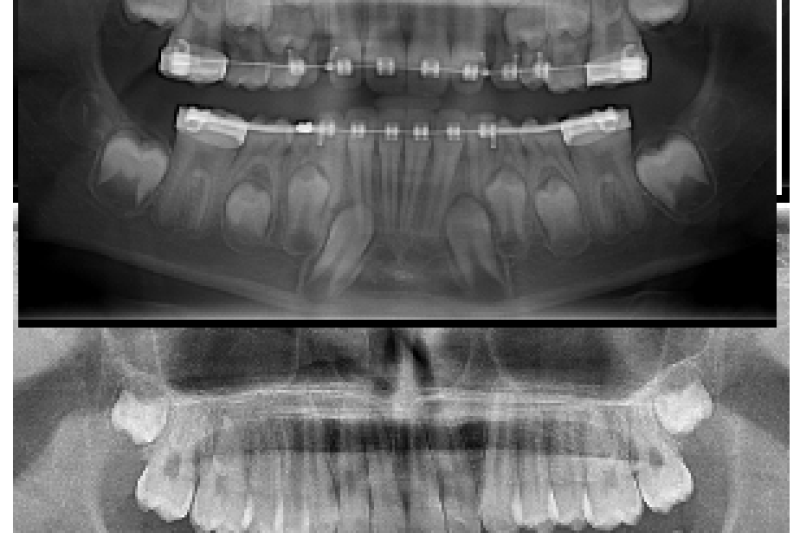

Been doing this for 19y, but I’m still amazed how my work can change a person’s look/life in just a year!